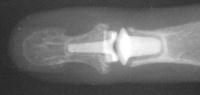

Final implant radiographs.

Xrays one year out.